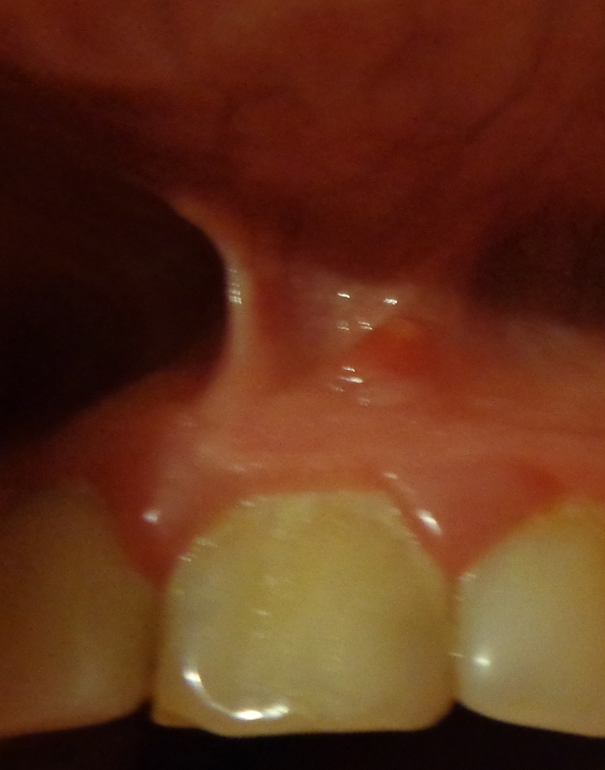

Прошло уже столько лет, а меня периодически беспокоит ноющая боль в десне над этим зубом. Вместо одного свища, образовалось ещё три.

Пошла к стоматологу она сказала "это хронически и не лечится уже". Я не успокоилась пошла к заведующей. еле уговорила сделать ренген. ( Его приложила).

Врач посмотрела и говорит что нужно канал раскрывать и лечить. Проконсультировалась с другим в платной, там вообще говорит что нужно уже резекцию корня делать. Подскажите пожалуйста что видно по ренгену?

Интересует качество пломбировки канала и вообще что Вы бы порекомендовали? ( Резекцию или заново канал делать?)